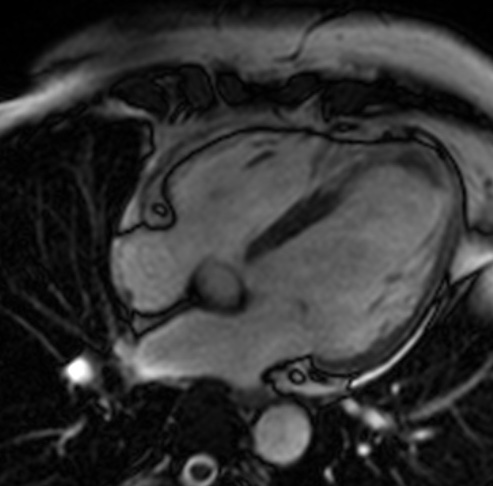

Ischemic cardiomyopathy involving LAD and partly LCX territory

There is focal T2 hypointense non enhancing soft issue seen in apical region of left ventricle most likely representing apical thrombus.

There is transmural enhancement seen in the apical, apical anterior, apical septal, apical inferior,  mid-ant septal, mid inf-septal segments ( segments17, 13,14,15,8,9). It probably represents scar tissue of non viable myocardium.